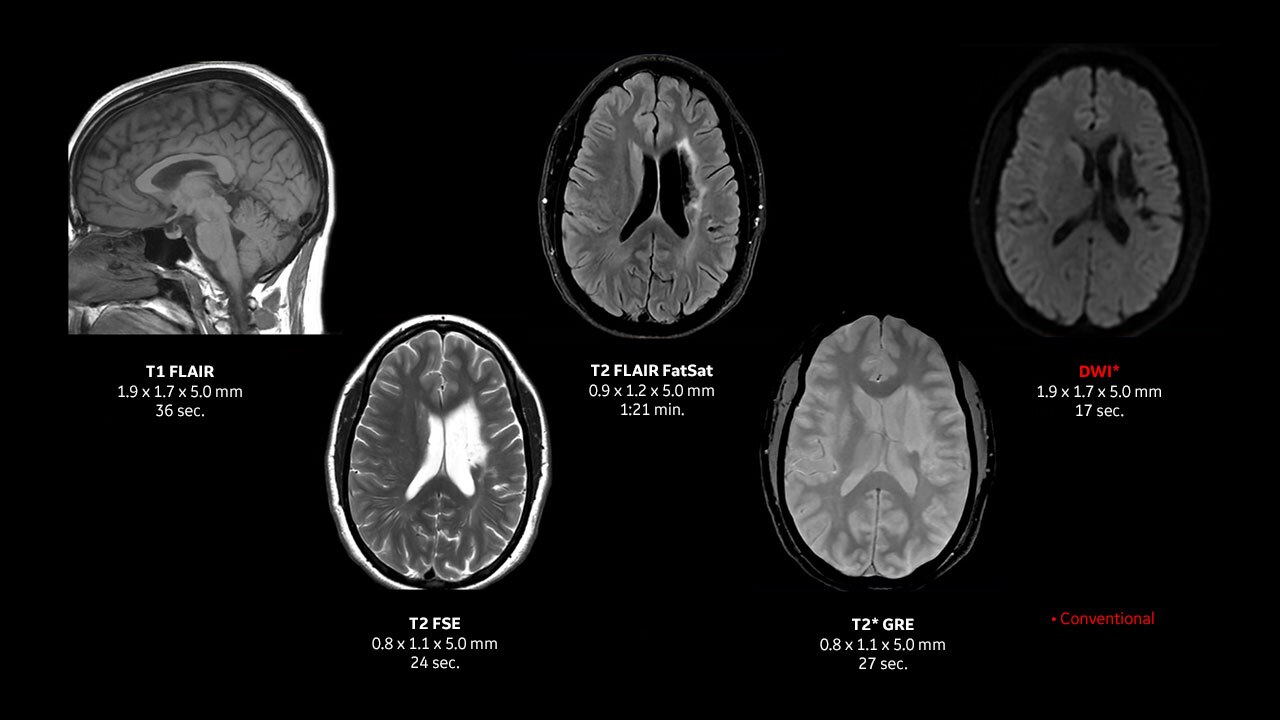

See what you need to see with TrueFidelity

For years, low dose was the benchmark for image quality by which every CT image was held. We helped set the standard for low-dose imaging back in 2008 by introducing the industry’s first iterative reconstruction technology capable of lowering dose. Over the years, the benchmark has changed. While dose is still important, radiologists are looking for an image texture reminiscent of the text-book quality images they studied in medical school.

Take your CT experience even further on a system designed for TrueFidelity, our latest innovation in CT image reconstruction technology that uses a deep-learning based reconstruction engine to combine the low-dose CT you expect with the image texture you want.